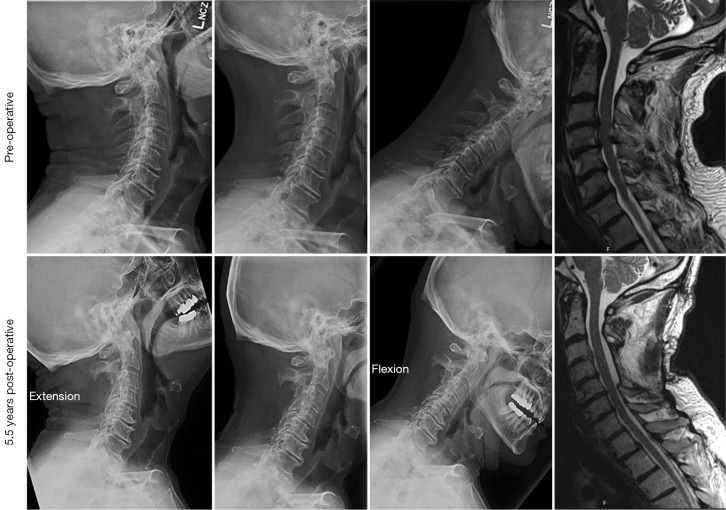

Background: Cervical laminectomy may be underutilized in the treatment of cervical spondylotic myelopathy (CSM) due to concerns regarding potential for post-operative instability and/or kyphosis. The purpose of this retrospective, observational study is to assess the short-term clinical and radiological outcomes as well as complications associated with a group of carefully selected patients who underwent laminectomy alone for CSM and compared them to a cohort of patients who underwent laminectomy with fusion.

Methods: Patients with CSM were identified via review of a single surgeon's cases. All patients underwent preoperative clinical evaluation, lateral flexion-extension cervical radiographs, and documentation of neck and/or extremity pain via Nurick Scale and modified Japanese Orthopedic Association (JOA) scores. Postoperative follow-up occurred at 1, 3 and 6 months for all patients. Statistical analysis was performed via Student's t-test for parametric values and Wilcoxon (Mann-Whitney) rank sum test for ordinal scores. Multi-variable linear regression was used to correct for co-variance.

Results: Forty-one patients who underwent laminectomy alone and 13 patients who underwent laminectomy with fusion were identified who met inclusion criteria. Both groups demonstrated significant improvement on Nurick and JOA scores postoperatively. Two patients in the laminectomy alone group required a subsequent one-level anterior cervical discectomy and fusion for onset of postoperative neck pain, without neurological symptoms or new deficits in the follow up period. There was no difference in rates of post-operative kyphosis between the groups.

Conclusions: In appropriately selected patients without pre-operative kyphosis or abnormal motion on flexion-extension films, cervical laminectomy remains a safe and effective treatment option.